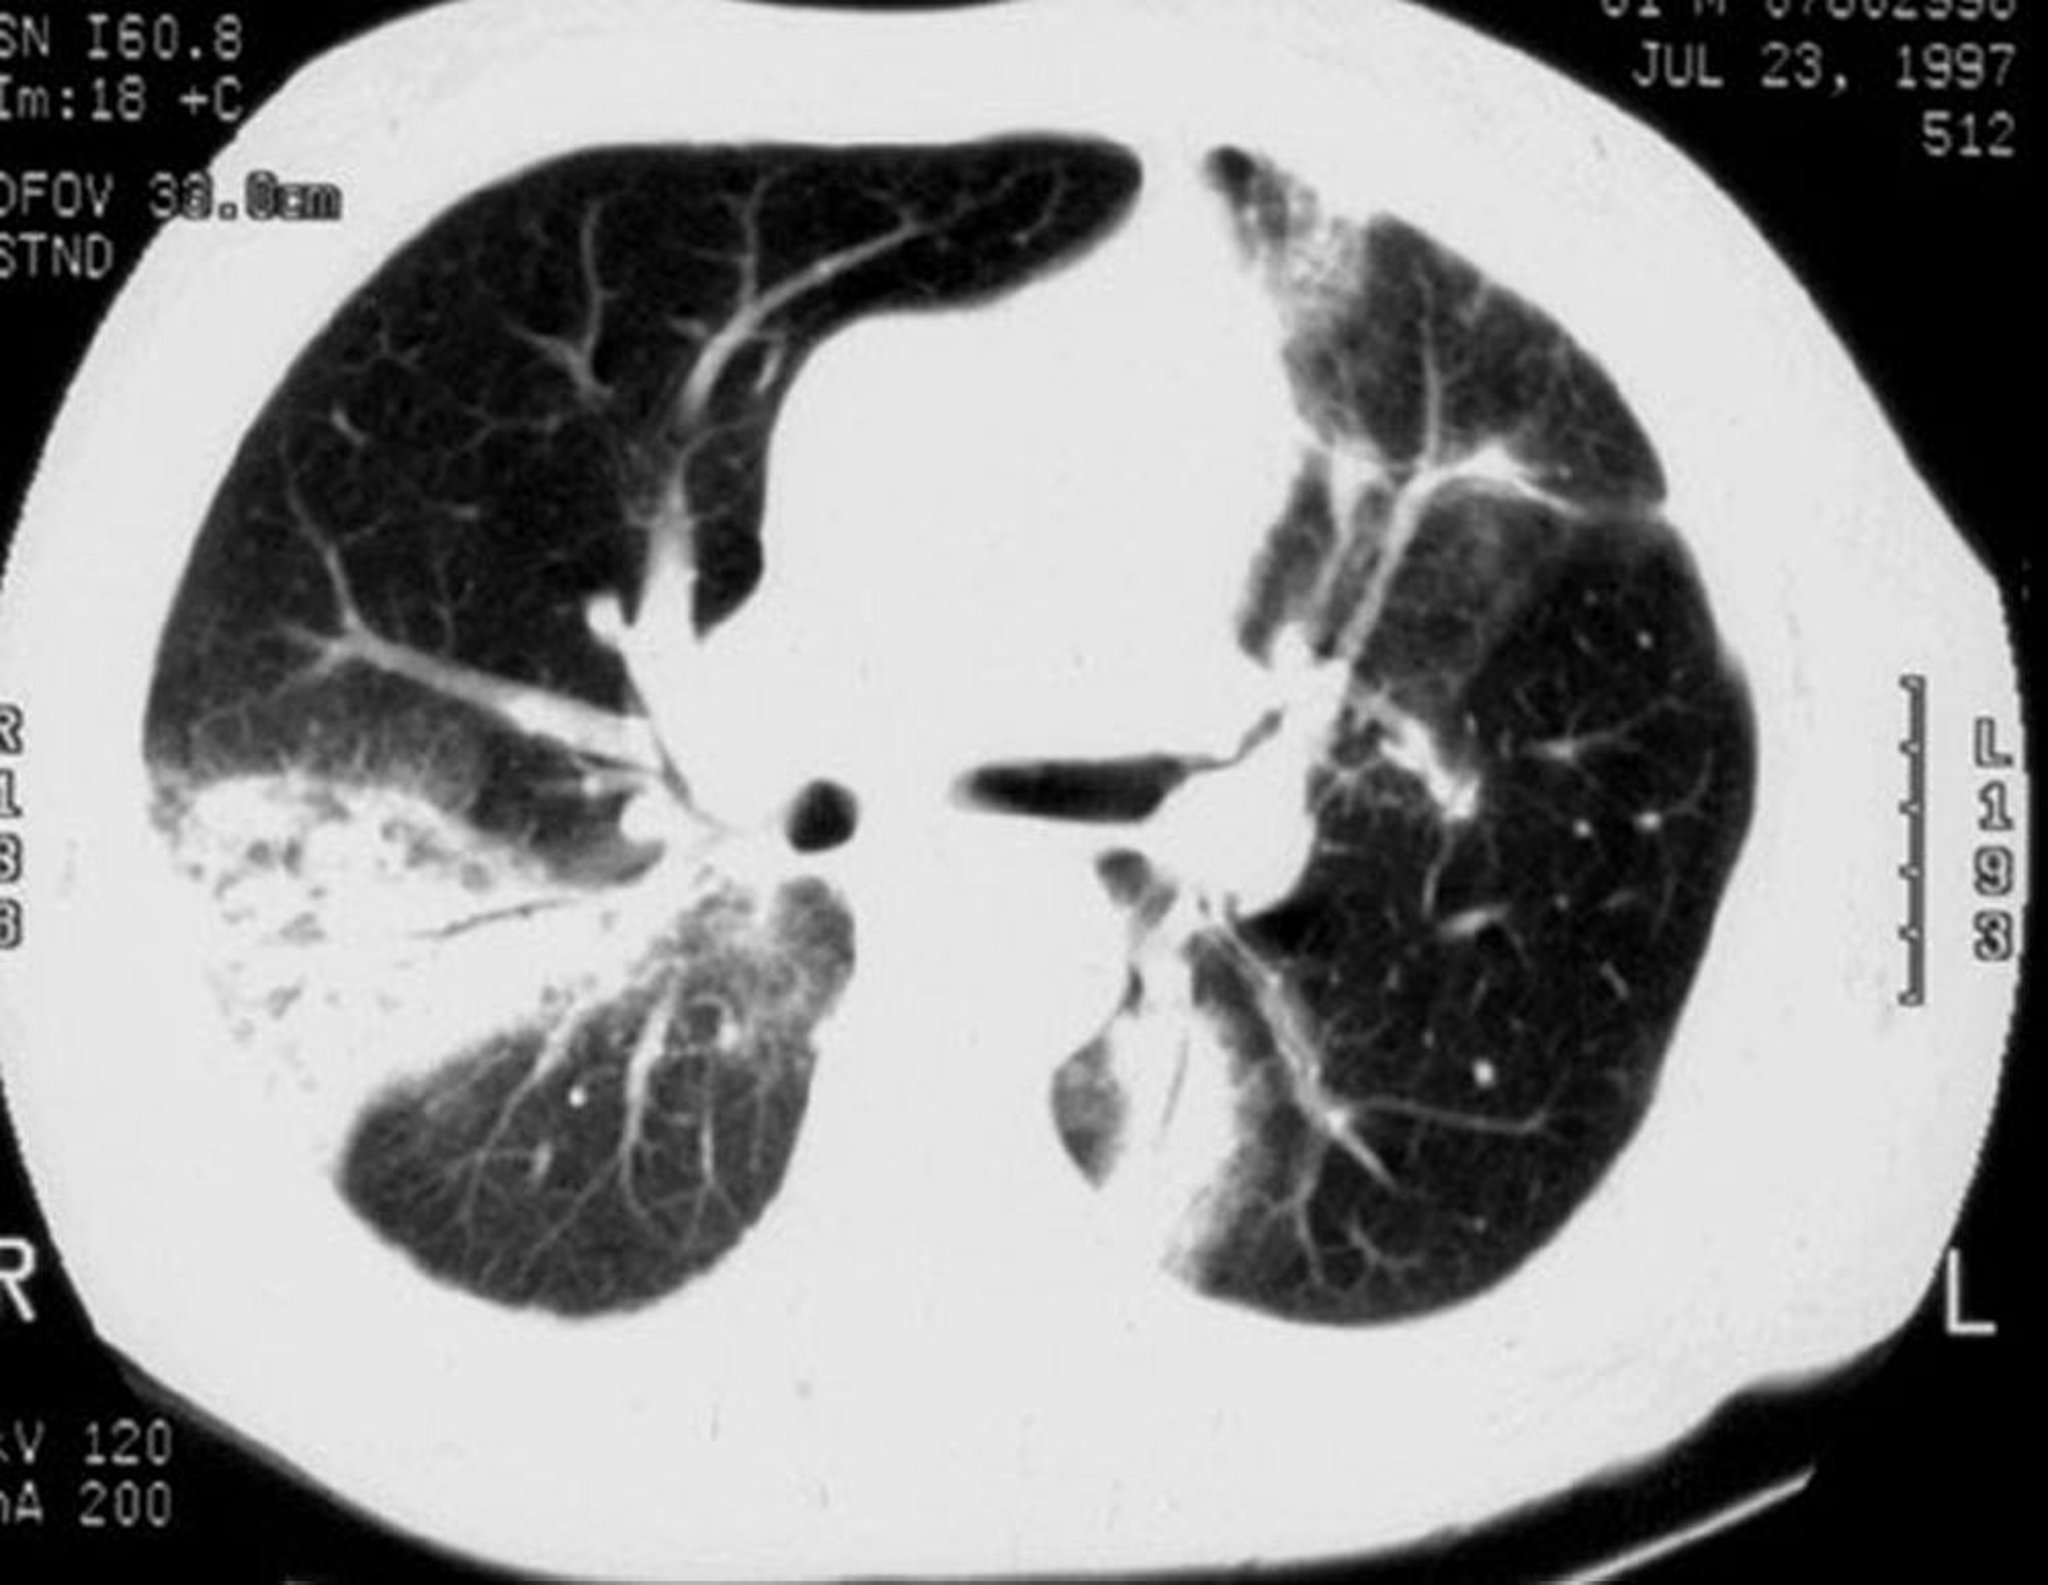

Polmonite criptogenetica organizzata

La TC ad alta risoluzione mostra addensamenti a chiazze degli spazi aerei, opacità a vetro smerigliato, piccole opacità nodulari e ispessimento e dilatazione delle pareti bronchiali (broncogramma aereo).

Image courtesy of Talmadge E. King, MD.